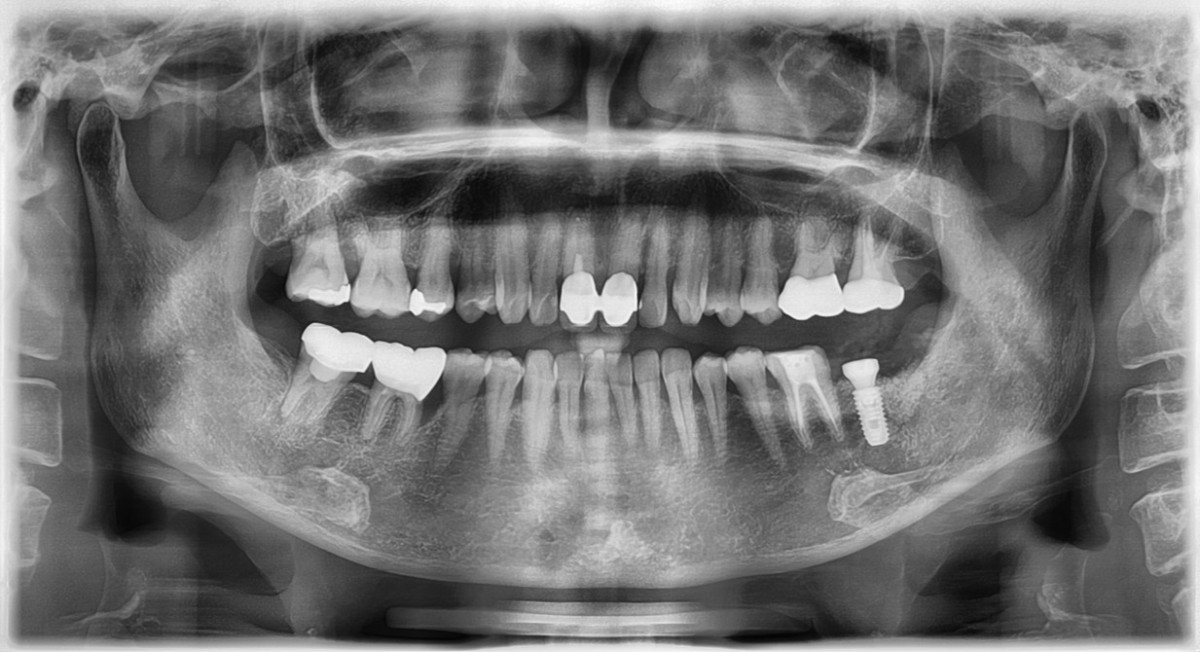

SIngle Implant - Immediate Placement, 8-year follow up

<CJ SBN> old female had mobility and pain when chewing in the lower molar